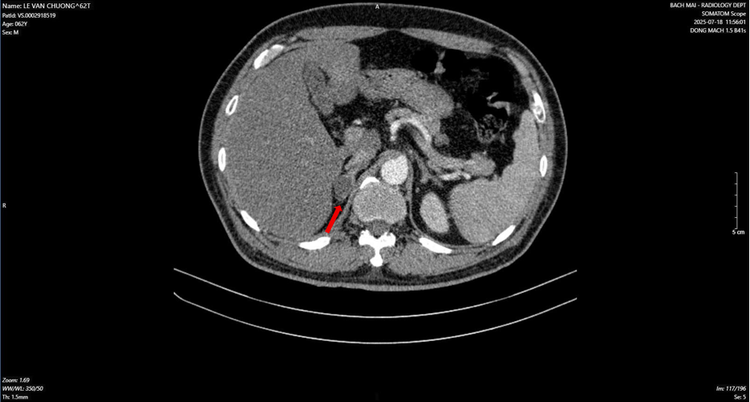

ung-thu-phoi.png

Hình ảnh dày tuyến thượng thận phải tạo nốt có kích thước 19 x 17 mm (mũi tên đỏ) - Ảnh BVCC